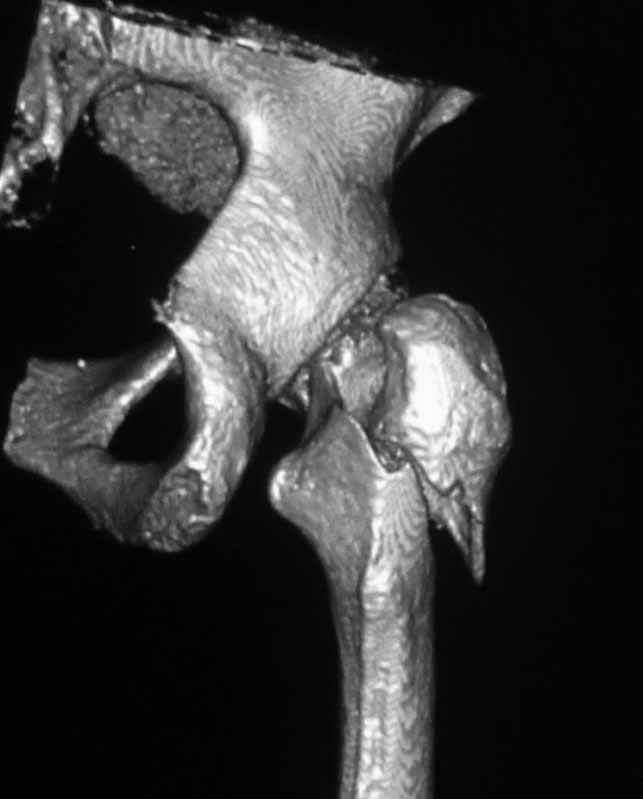

Пациентка 53 лет. ДТП 09.01.12: сочетанная травма: перелом 2-5 ребер справа, ушиб легких; перелом обеих лонных костей без смещения; закрытый перелом проксимального конца правой бедренной кости; открытый оскольчатый внутрисуставной перелом проксимальных концов костей правой голени.

В нашей клинике 11.01 выполнен минимально инвазивный остеосинтез большеберцовой кости (снимки до операции не перефотографировал) с пластикой перемещенными лоскутами дефекта, образовавшегося вследствие некроза кожи на передней поверхности голени. Бедро одномоментно делать не стал, не было уверенности в наличии перелома на уровне шейки. Во время операции смотрел тазобедренный сустав под ЭОПом, головка неподвижна. После операции повторили КТ, стало очевидно, что имеется субкапитальный перелом.

Учитывая тяжесть, возраст больной, а также характер перелома - чрезвертельный оскольчатый осложненный переломом костей таза о остеосинтезе как методе речи быть не может. Вертлужная впадина по КТ выглядит обнадёживающе лишь на первый взгляд - коксартроз и нещадящий остеопороз своё дело сделал. Надо уменьшить шоковый индекс и тяжесть травмы вот в чем дилема, а наносить травму, каковой операция является на раннем этапе несколько опасно. Золотое правило - срочности в ортопедии нет - здесь работает. Сустав однозначно нужно менять, но позже, когда состояние будет абсолютно стабильным, т.к. после травмы появятся подстёгиваемые гиподинамией "подснежники",активно привлекайте смежных специалистов - терапевта, невролога, эндокринолога. Вытяжение за пятку не достаточно, замените, за невозможностью через бугристость болшеберцовой кости, вытяжением через мыщелки бедра (интактным оно уже не является), плюс боковое вытяжение за проксимальную часть бедра посредством тяги за введенный стержень Кюнчера (допустима тяга порядка 6 килограмм!!) Лечение на пол месяца.Далее пациентку, если она не абсолютная бабушка,ждёт этапная операция, если возникнет необходимость, т.к.инвалидизация лучше чем полное обездвиживание. Стержень с блокированием (PFN) средней длины но не короткий (Вы заикнулись о ЭОПе, значит навык есть.). Не торопитесь коллега. Чуть не забыл, тотальное протезирова ние редко используется в сочетании с блокированным остеосинтезом по причине большого дефекта костных структур,выбирать Вам.Вопрос тяжелый и требует более опытного взгляда, чем мой. Как говорится, за спрос не бьют. Извините, что не смог помочь лучше.

Если позволяет состояние - надо штифтовать, как раз сейчас, есть подходящее "окно". Любым проксимальным гвоздем, можно коротким. Об артропластике думать пока рано, перелом шейки - вколоченный, стабилизируется in situ.